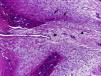

Mujer de 29 años, que consulta por tumefacción y dolor en el quinto dedo de la mano izquierda, de 3 meses de evolución. No presentaba antecedentes médicos de interés y no refería traumatismo previo en el dedo. A la exploración, presentaba una tumoración de 1,5×0,5cm en el pulpejo y la región subungueal, de consistencia indurada, adherida a planos profundos, con eritema leve y dolor a la palpación. El estudio radiológico mostraba una lesión nodular osificada, bien delimitada, de bordes irregulares, adherida al periostio de la falange distal del dedo afectado, sin erosión de la cortical (fig. 1). La analítica, incluyendo bioquímica, hemograma y reactantes de fase aguda, fue normal. Se realizó la exéresis de la lesión y el estudio histopatológico reveló que estaba constituida por tejido fibroso con fibroblastos con núcleos prominentes sin atipia en su periferia y depósitos de osteoide inmaduro rodeados por un ribete osteoblástico en su zona central (fig. 2). Dichos hallazgos fueron compatibles con el diagnóstico de periostitis reactiva florida de la mano (PRFM). No hubo recidivas de la lesión.

La PRFM es una entidad benigna rara caracterizada por una exuberante producción osteoblástica en un estroma fibroso proliferativo originada a nivel del periostio de los dedos1. Su patogenia es desconocida, pero se considera que corresponde más a un proceso reactivo que a una neoplasia, estando presente el antecedente traumático hasta en un 50% de los casos2. Aunque fue descrita en 19333, existe hasta la fecha importante confusión en la literatura debido a sus diferentes denominaciones, que incluyen fascitis paraostal, fascitis osificante, seudotumor fibro-óseo, tumor óseo seudomaligno de los tejidos blandos de los dedos y fascitis nodular, siendo PRFM la más aceptada2,4. Se localiza con mayor frecuencia en la falange proximal, seguida por la falange media, metacarpianos y falange distal, siendo rara en el primer dedo2. Ocurre generalmente en mujeres durante la segunda y tercera décadas de vida, y clínicamente se caracteriza por tumefacción, dolor y eritema del dedo afectado2,5. Las radiografías muestran aumento de partes blandas y neoformación ósea perióstica, que puede tener un aspecto lamelar o de hueso maduro5. La cortical generalmente está intacta, aunque se han descrito ocasionalmente erosiones6. El diagnóstico diferencial incluye infecciones (tenosinovitis séptica, absceso de partes blandas con alcance óseo, osteomielitis cortical), miositis osificante, tumores benignos como el de células gigantes de la vaina tendinosa y el osteocondroma, y malignos como el osteosarcoma paraostal y periostal, el sarcoma sinovial y el condrosarcoma periostal1,5. El tratamiento recomendado es la escisión local, que es curativa en la mayoría de los casos5. En conclusión, aunque la PRFM es una lesión infrecuente, conviene tenerla en cuenta debido a que puede simular otros procesos más graves, como las neoplasias óseas malignas.